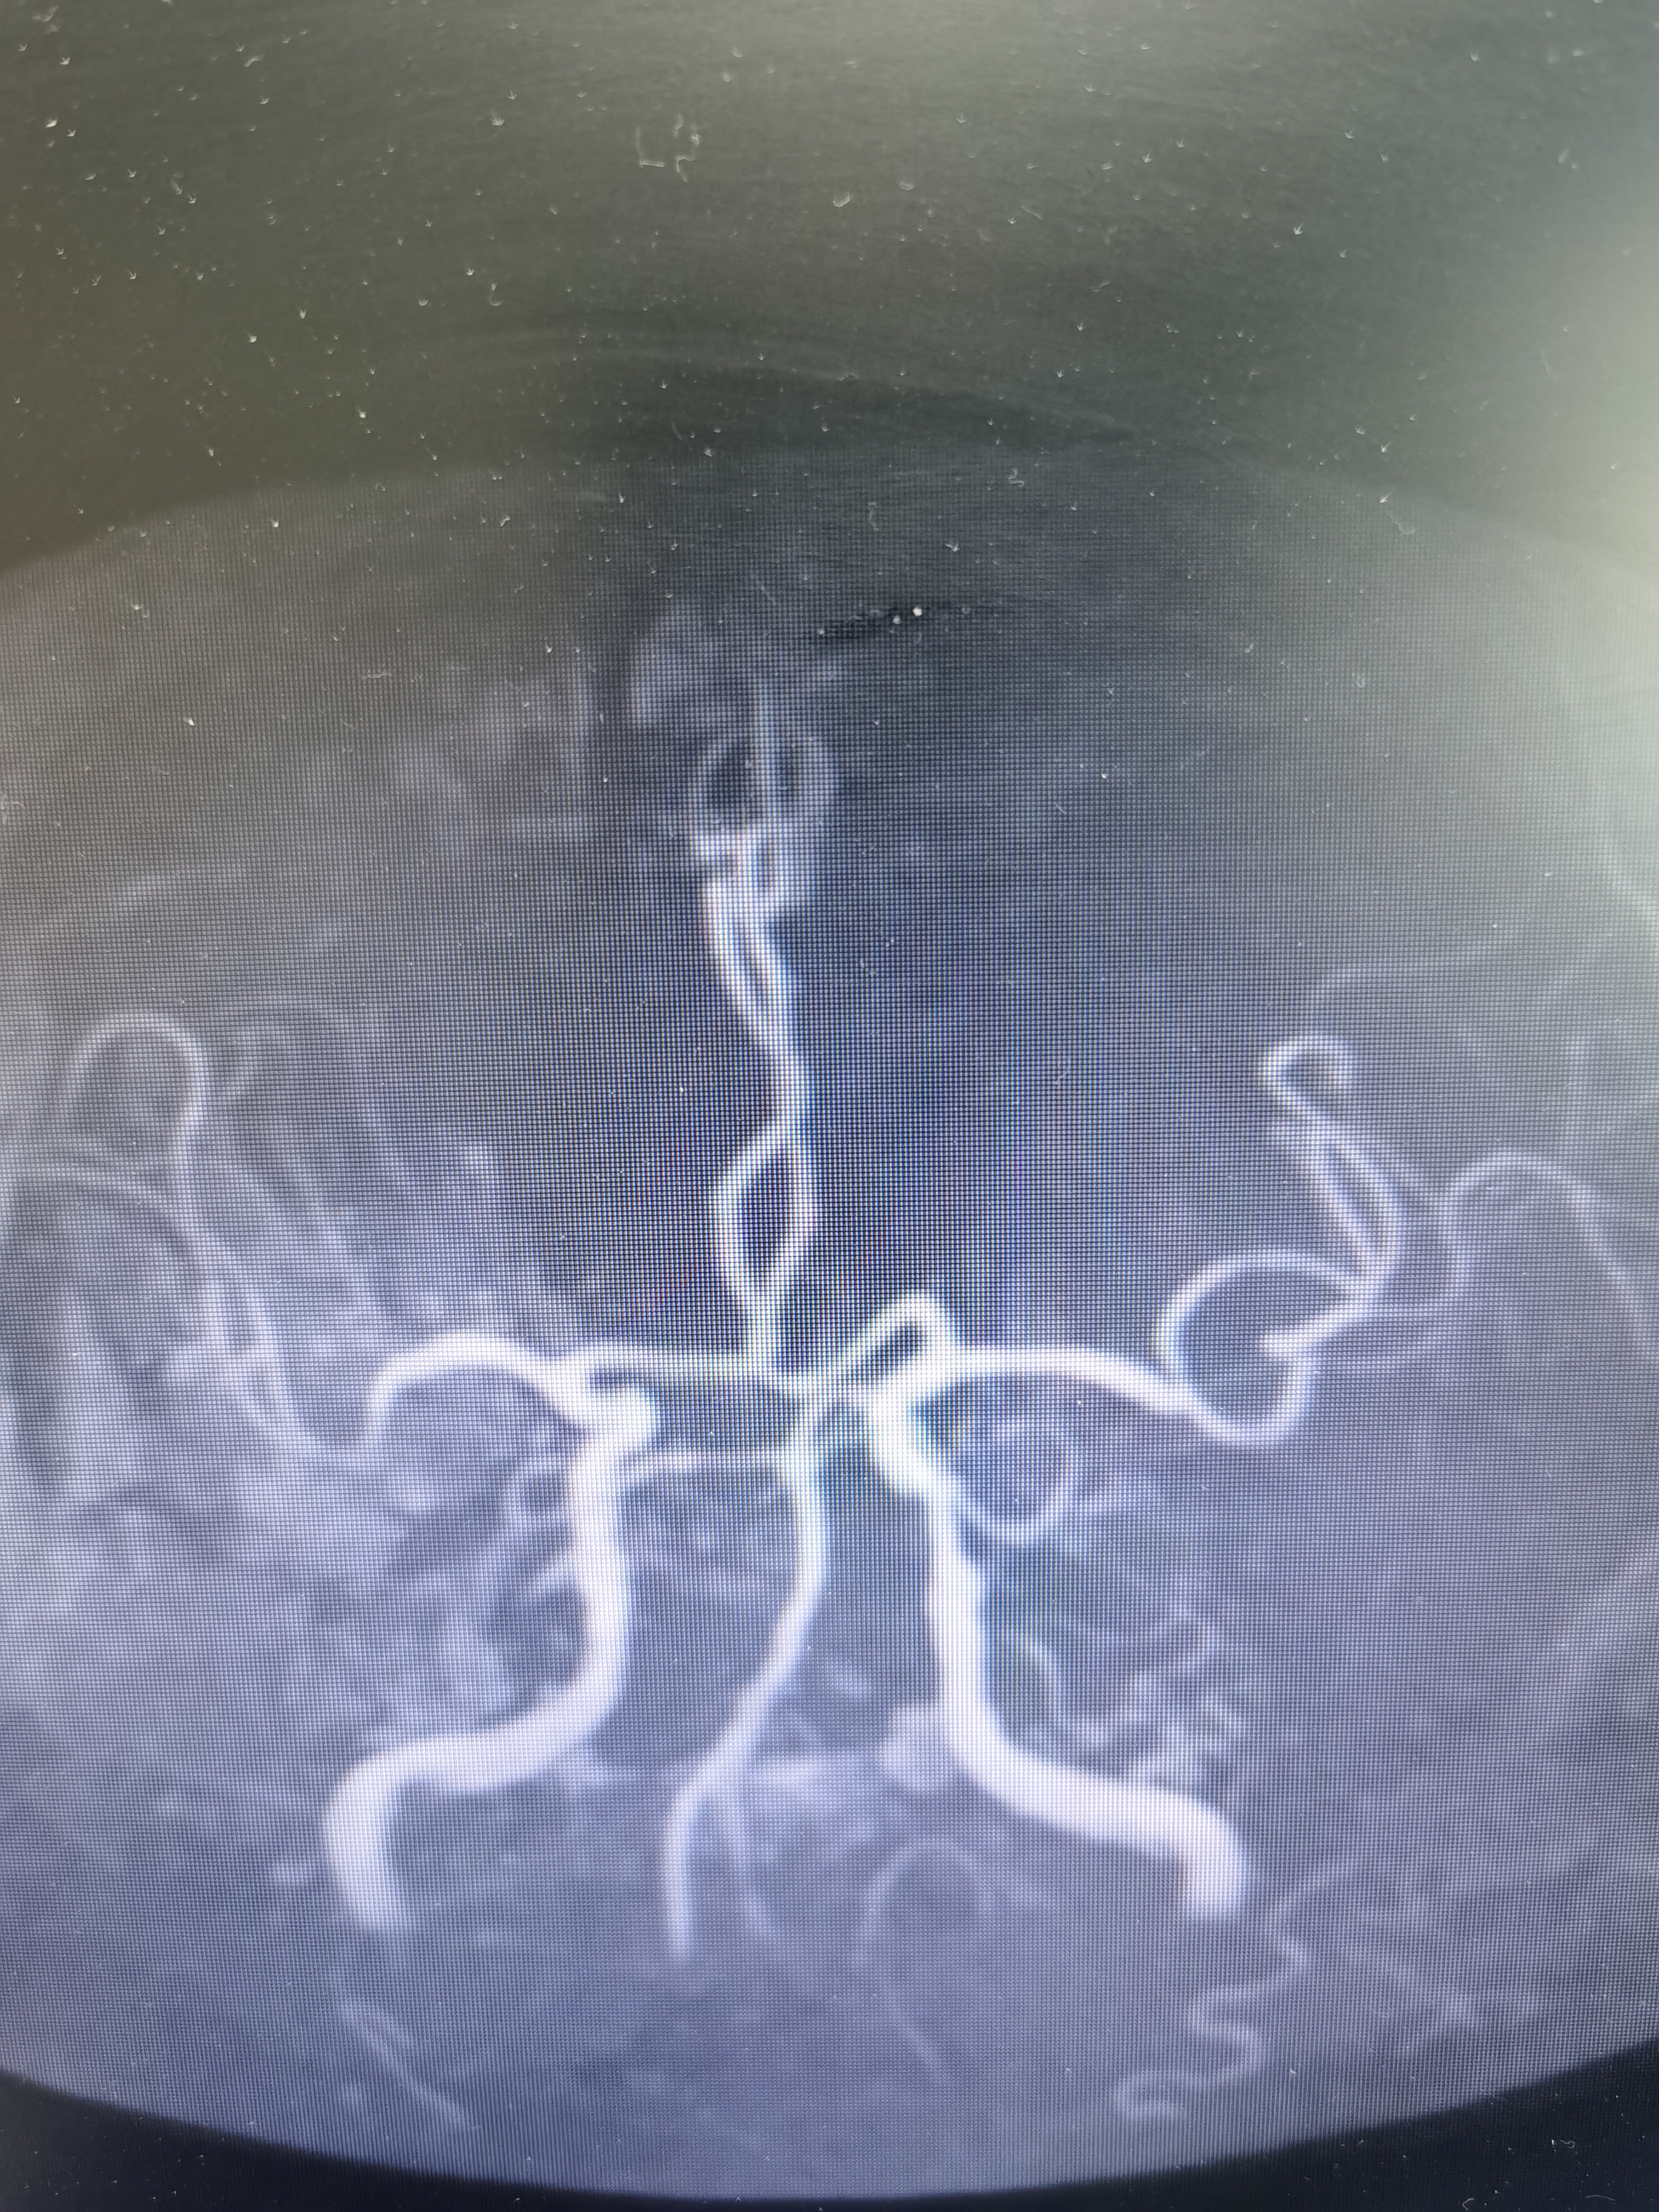

MRA示颅内血管动脉硬化改变。

DSA示右椎动脉优势,起始部极重度狭窄,左侧椎动脉完全反向血流,动脉晚期可见左侧锁骨下动脉闭塞端。